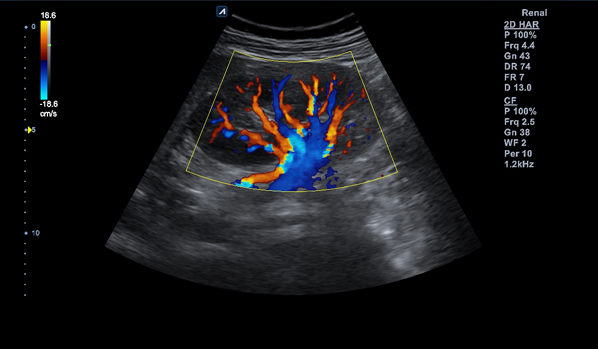

C1-6CT

C-Architecture (PowerView™)

Convex transducer (1-6MHz)

Application:

Abdomen, EM, Gynecology, Obstetrics